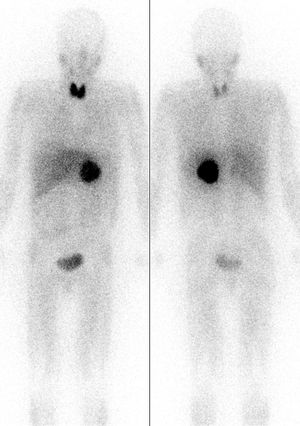

| 진단 | 혈장 유리 메타네프린 상승, 혈장 카테콜아민 상승, 소변 카테콜아민 상승, MRI, PET 스캔 |

영상 검사로는 CT, MRI, 131I-MIBG 신티그래피, PET 등이 있다.[82] CT와 MRI는 종양의 위치, 크기, 주변 구조와의 관계를 파악하는 데 유용하다.[82] 131I-MIBG 신티그래피는 부신 외 원발 병변이나 전이 병변의 위치를 확인하는 데 사용된다.[88] MIBG는 노르에피네프린과 유사한 구조를 가져 종양 세포에 섭취되는 원리를 이용한다. PET 검사는 MIBG 섭취가 없는 경우에도 양성으로 나타날 수 있으며, 전이 병변 검색에 유용하다.[90] 특히, 68Ga-DOTA 유사체를 이용한 PET 검사는 소마토스타틴 수용체 영상 기법으로, 다른 기능적 영상 검사보다 우수한 성능을 보인다.[94][95][97]